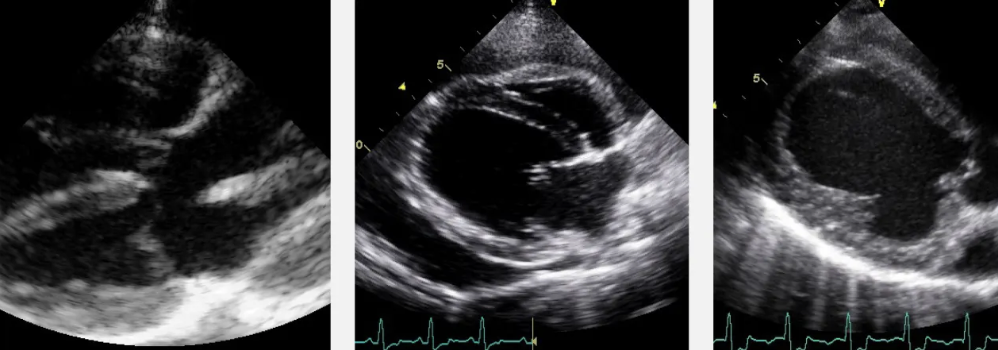

this view is short-axis

How well did you know this?